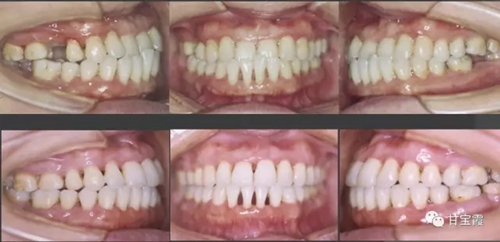

經(jīng)過(guò)一年多的正畸治療,關(guān)閉了所有的缺牙間隙,也不用再鑲牙了。

上圖為矯正前后的對(duì)比

其實(shí)她可以選擇種三顆牙,也可以選擇做九顆烤瓷牙,但是她最終還是選擇了用正畸的方法關(guān)閉間隙,這是一個(gè)明智的選擇。同時(shí)還解決了前牙的反頜達(dá)到了美觀的效果。